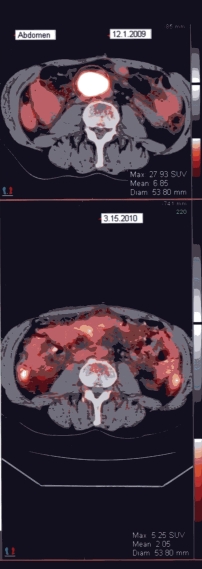

Tues 12/1/09 - It is hard to imagine that we'd be happy about seeing a tumor on one of Chris' PET scans. Well, not happy exactly, but it was a better report for a change. The scan did show one active and growing tumor in his abdomen. Same tumor that has been the most problem from the beginning. But the scan also showed that the tumors that were radiated early this year are no longer active and are shrinking. Chris' oncologist was excited enough about it that he immediately recommended radiation (hard for a "chemo" doctor to do sometimes). So, Chris starts radiation on Monday. Because of some radiation overlap from previous treatment, he will be getting low dose treatments twice a day.

Fri 3/19/2010 - Chris had a PET scan on Monday. On Wednesday we got the results and it was the best news we could have hoped for. The PET was clean!!!! The radiologist called the results amazing! For the time being, Chris is in remission. There will be another PET scan in about four months. That will be the nerve wracking one.

PET Image

Amazing!

The whole report is here, if you'd like to read it. I've also uploaded a larger version of the actual scan.